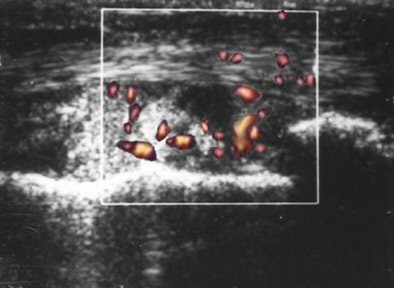

![]() |

| PDS shows markedly increased vascularity. |